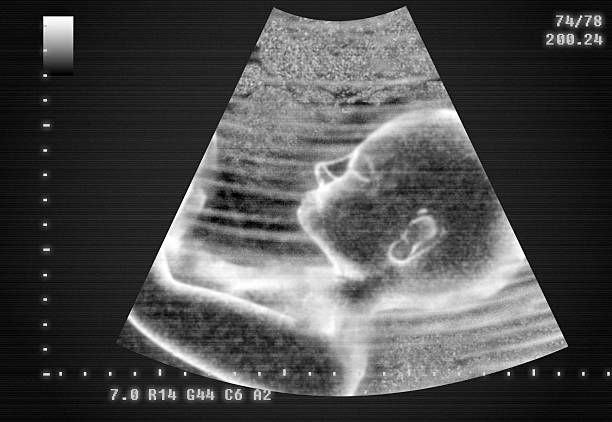

Auscultation involves listening to the sound of your baby’s heartbeat. This can be done using tools like a stethoscope, Doppler device, or electronic fetal monitors. The heart tones provide critical insights into your baby’s condition, including their heart rate, rhythm, and overall health. Regular auscultation ensures the baby receives adequate oxygen and is developing normally.

If abnormalities are detected, your doctor may recommend further tests like an ultrasound or continuous electronic monitoring.